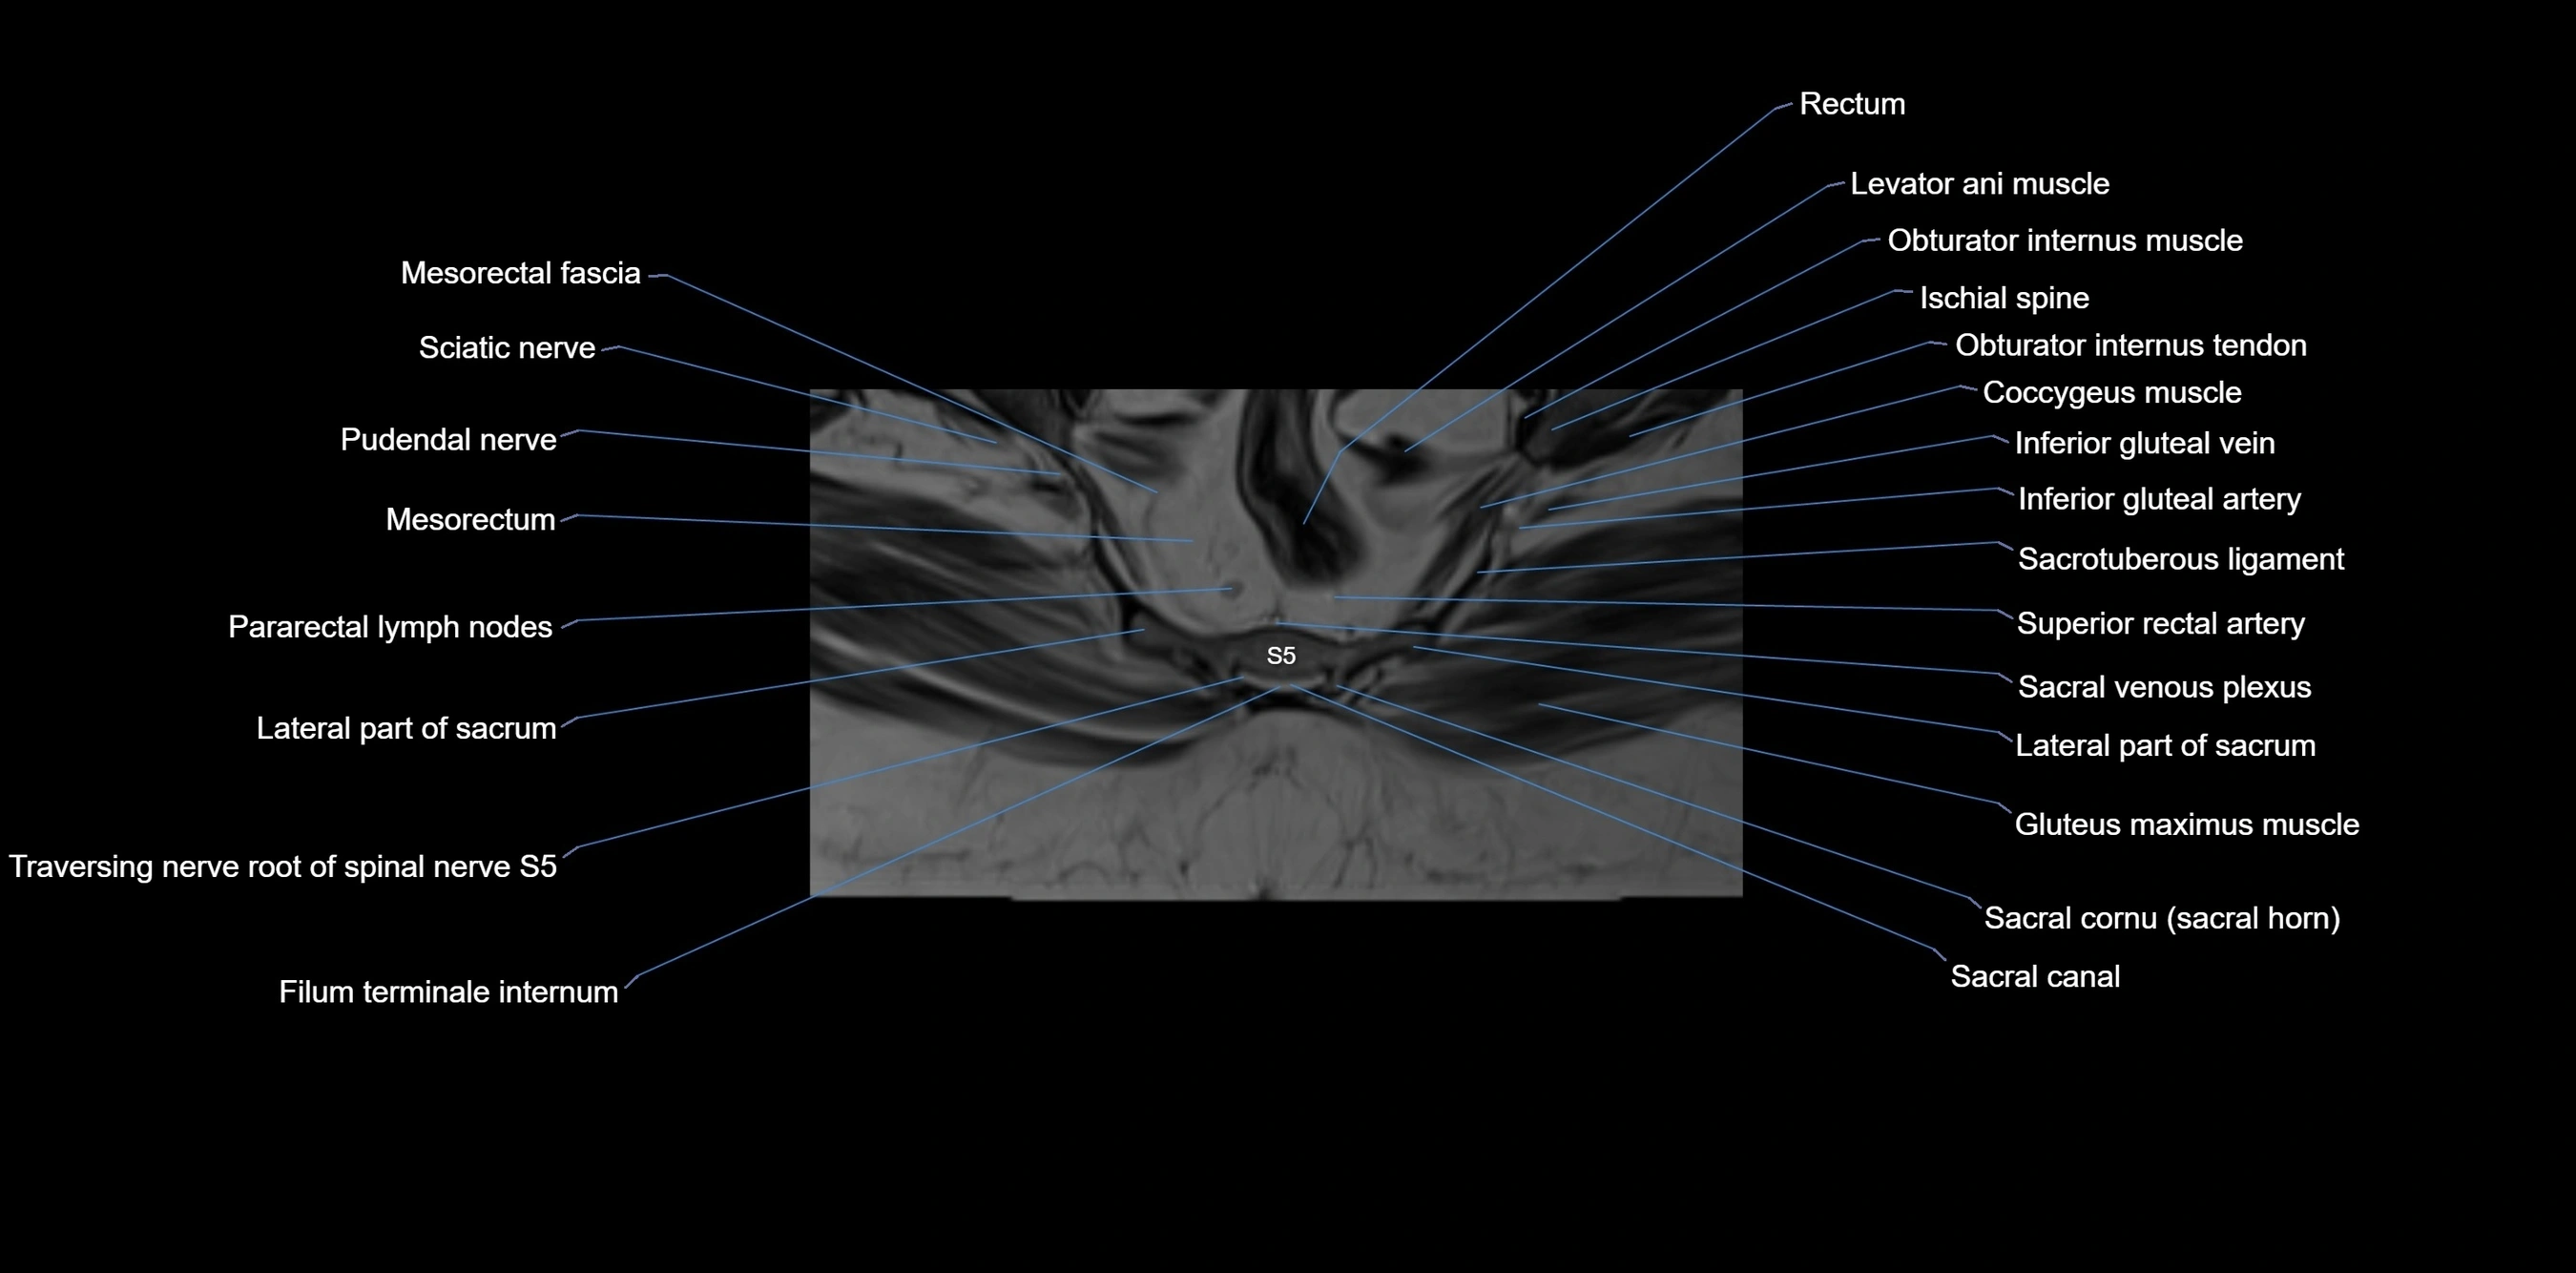

CT image

image